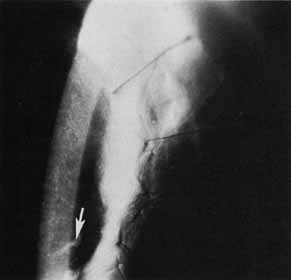

It is at this point that we take what is the last of a series of intraoperative steps designed to minimize astigmatism. Before placing the running suture, we perform qualitative keratoscopy using a von Luhnen keratoscope. Other methods may be employed, such as the use of circular metal loop on a handle (Fig. 10), or an operating microscope-mounted qualitative keratometer. The Flieringa's ring, if present, is removed. Intraocular pressure is adjusted by filling the anterior chamber. The keratoscope or wire loop is held about 2 cm directly above and parallel to the plane of the cornea. Irrigation of the graft will smooth the surface enough to see a reflection of the loop on the cornea. Most commonly, the reflection is ovoid, which indicates astigmatism of the graft; the short axis represents the steepest curvature of the cornea. Suture tension is adjusted by loosening or tightening the slip knots. Keratoscopy is repeated with additional suture adjustment as needed to minimize the corneal astigmatism. When the adjustments are completed, a final throw is placed on each suture, and the knots cut short with Vannas scissors. Burying the knots in any type of corneal surgery is essential. The knots are buried into the donor stroma in an attempt to keep them as far away from any vascularization as possible. Anteroposterior graft–host disparity in alignment can also induce astigmatism and should be identified. Sometimes a meridian is flat because the donor is anteriorly displaced or steep secondary to posterior displacement. Resuturing is then necessary to correct the problem. It is not uncommon to inadvertently take superficial bites on the recipient side when suturing away from oneself.

Fig. 10 Wire-loop keratoscope is held between the cornea and microscope. An oval image narrower at the 90-degree axis indicates corneal astigmatism with the steeper curvature at 90 degrees.